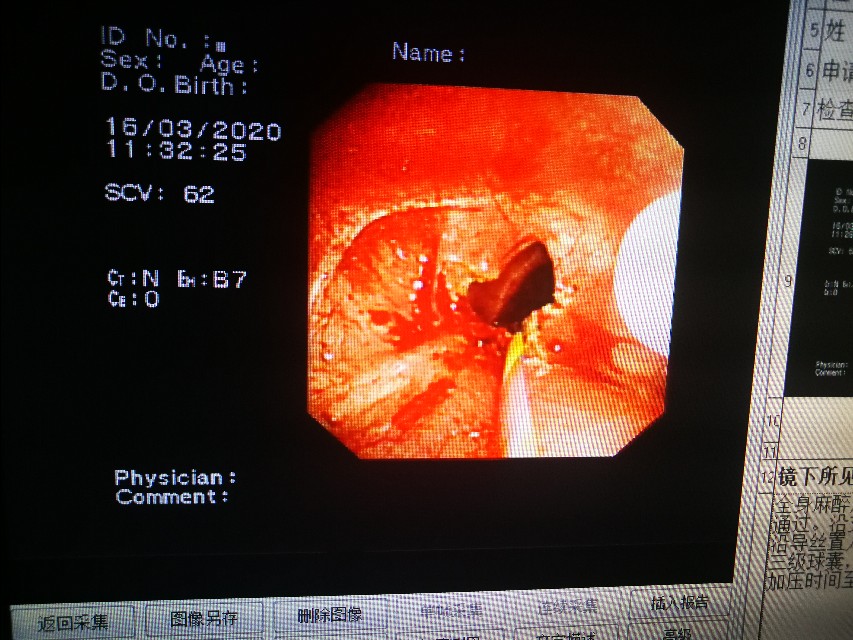

气管镜下可以更直观的看到气管到底多狭窄。只剩下几毫米的小孔了。

八点钟方向一刀下去,狭窄处撕开一个口子,还好出血不多。紧接着,又再其他位置放射壮切开。球囊打进水,慢慢的撑起来,这个时间患者是一点呼吸也没有的!时间一秒一秒过,患者血氧轻度下降,停止操作,给氧!指标慢慢好转,反复再做,压力一点点增加。

成功了!

四天后,我们又冷冻了狭窄处的边缘,并且再次扩张。患者反应非常好,呼吸顺畅多了。